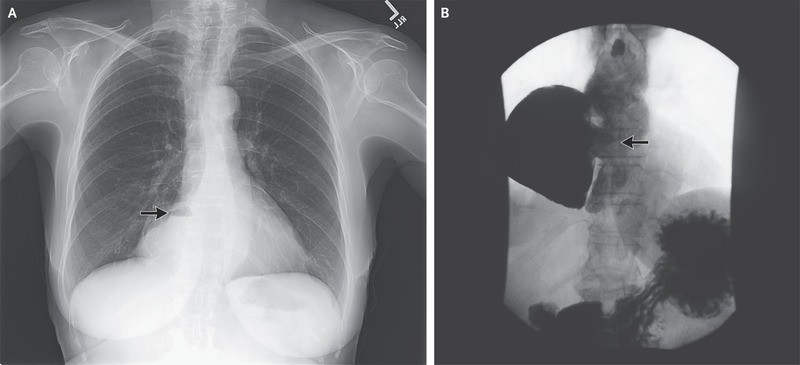

A chest radiograph showed a density containing an air–fluid level to the right of the heart (Panel A, arrow). Radiography of the esophagus revealed an epiphrenic diverticulum, 10 by 15 cm (Panel B, arrow), and delayed emptying at the gastroesophageal junction with esophageal dilatation and tortuosity, which are findings consistent with the patient’s diagnosis of achalasia.